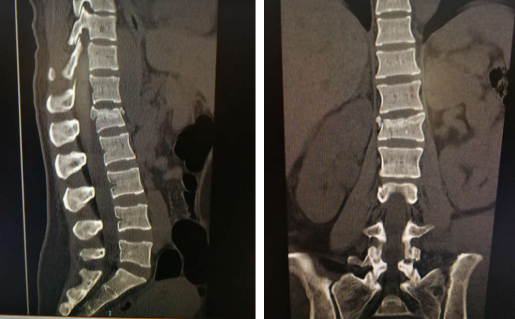

术前

脊柱科孟磊副主任医师接诊,武大姐腰1椎体骨折,左侧髂骨骨折、左耻骨上下支骨折,为保证能又快又好地恢复,需要进行手术固定治疗。脊柱科尚军主任和手术小组经过讨论,一同制订了安全高效的手术方案——利用骨科手术机器人辅助微创治疗腰椎骨折。因为传统的内固定手术方式对患者而言,创伤大、出血多、手术时间长、术后恢复相对较慢。

第二天,尚军主任孟磊医生手术小组为患者进行了第一次手术:在骨科机器人辅助下进行腰椎骨折复位内固定术,以及左股骨髁上骨牵引术。